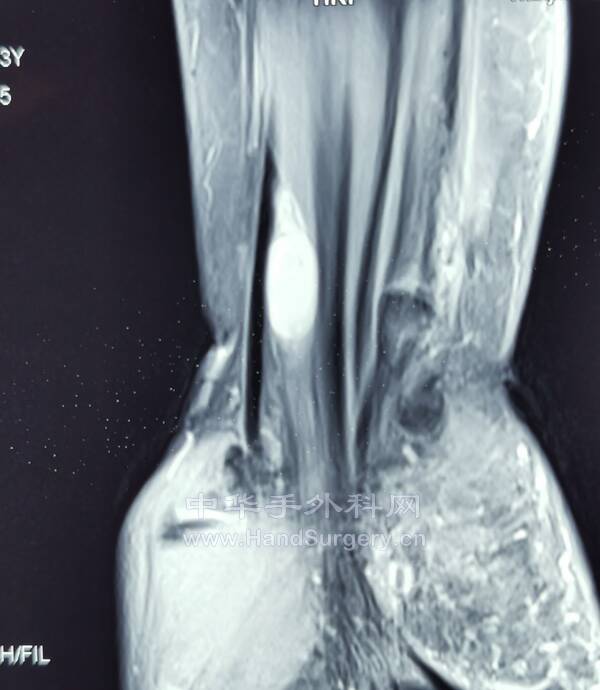

腱鞘巨细胞瘤(黄色素瘤)

沿郎格氏线设计切口